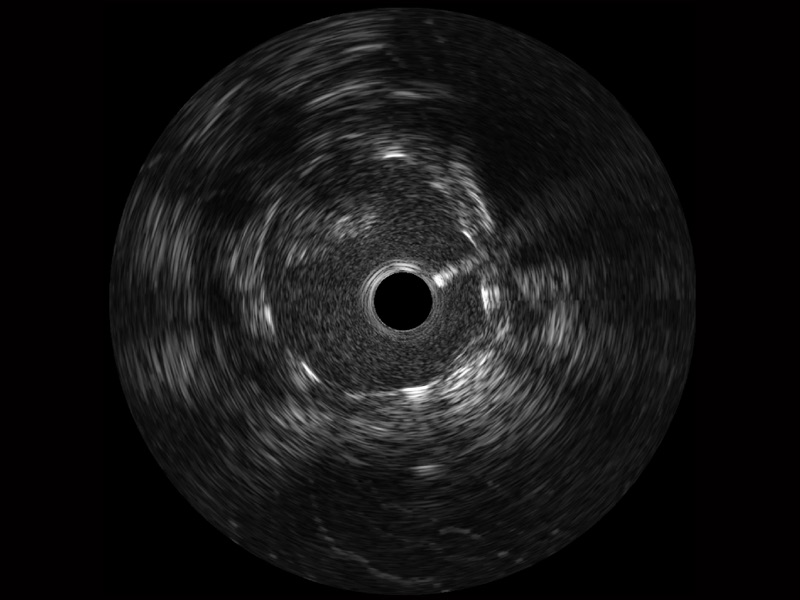

临床图

远场分支血管及导丝

组织脱垂